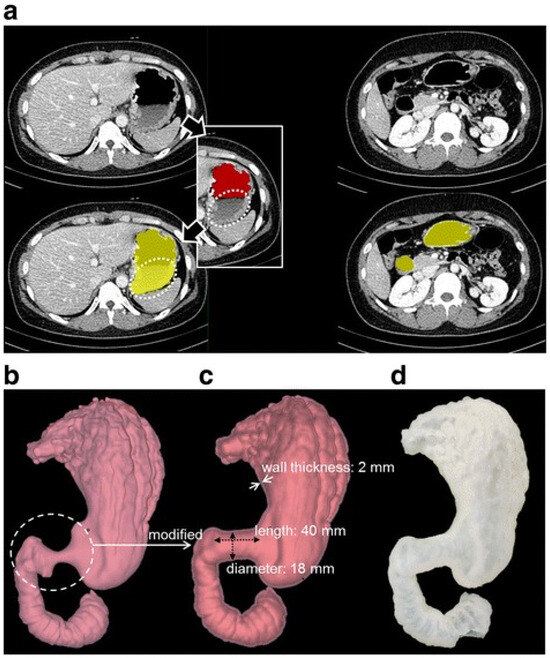

The most common 3D-printed gastrointestinal organs are the stomach, colon, and esophagus. Most studies have focused on specific training and preoperative evaluation for surgeries and other procedures related to the gastrointestinal tract. The current 3D gastrointestinal models are patient-specific ones derived from real patient imaging data. Only six studies mentioned the dimensions of these models [21,24,32,35,39,40]. Figure 6 shows the process of generating 3D-printed models from image post-processing and the segmentation of original CT images to a 3D model’s development.

Figure 6. Process for preparing a 3D-printed gastroduodenal (GD) model from CT gastrography data. (a) CT images with segmentation masks. A red mask was made using a simple thresholding setting. Yellow masks were the final segmentation result after multi-step imaging. (b) Initial 3D GD digital model. (c) Modified 3D GD digital model for stent placement. (d) Anthropomorphic 3D-printed GD phantom model. Reprinted with permission under open access from Kim et al. [21].

According to the 25 studies, 3D-printed gastrointestinal organs included the entire digestive tract. In 10 articles (40%), the stomach was the most frequently modeled organ [18,21,24,25,27,28,29,32,38,42] (Figure 4). Three-dimensional-printed rectum models were reported in only three studies [19,22,41]. The thickness of the gastric wall ranged from 2 mm to 4 mm [21,24,32]. One study mentioned the wall thickness of the colon was 2–3 mm [40]. Two studies reported the dimensions of the gastrointestinal tract models (the gastric outlet model was 40 mm in length and 18 mm in diameter, and the small bowel model was 30 cm in length) [21,35].